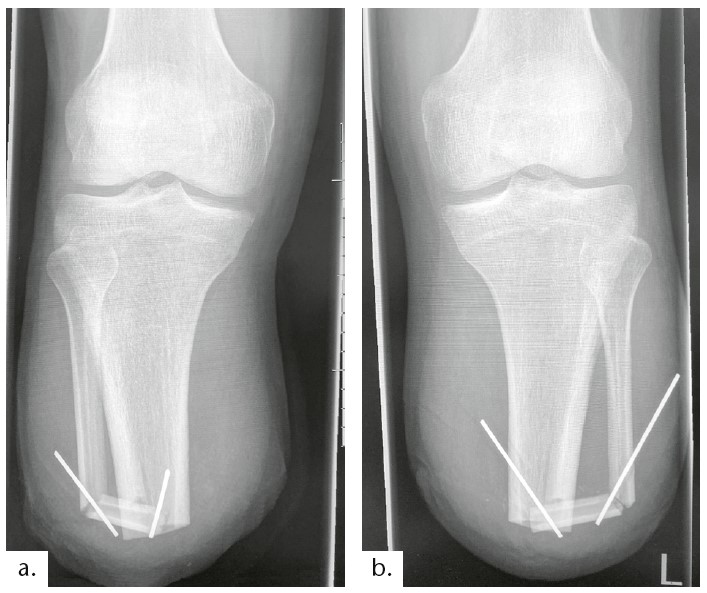

Statt einer Kortikalisschraube, einer Plattenosteosynthese oder eines nicht resorbierbaren Fadenmaterials (Tight Rope) entschieden sich die Operateure für je zwei passager einzubringende Kirschner-Drähte, die von schräg distal nach schräg proximal implantiert wurden (vgl. Abb. 1 und 5).

Die Röntgenkontrolle Anfang Dezember 2021 zeigte zwei stabile Brückensynostosen und bestätigte unsere geplante Vorgehensweise. Die sportlichen Aktivitäten des Anwenders konnten weiter erhöht werden. Je mehr Bodenreaktionskraft auf die distalen Knochenverbindungen wirkte, desto schneller fand die Durchbauung der Synostosen statt. (Abbildungen mit Röntgenbildern 10. Monat) Daher wurde in dieser Phase, im Januar 2022, mit der Anfertigung von Prothesen für sportliche Aktivitäten begonnen. Die speziellen Ansprüche erforderten einen klassischen Schaftrandverlauf an den dafür genutzten Prothesenschäften.